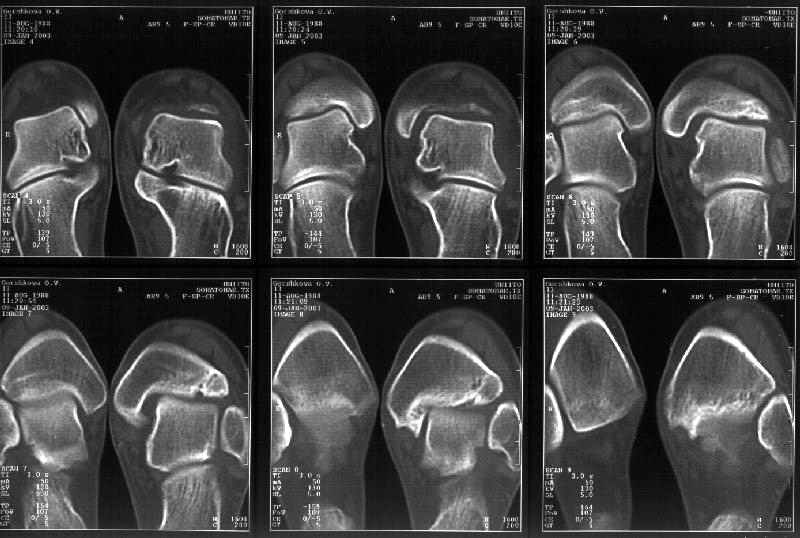

Re: Последствия травмы голеностопного сустава

Сегодня пациентке сделали сравнительную КТ. А ксиальные и Фронтальные срезы приложены. Ваше мнение?

Фронтальные

Аксиальные